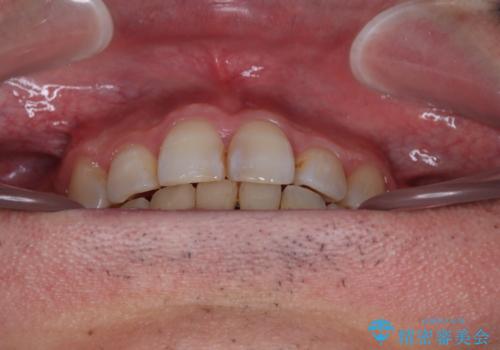

顎が左右にずれた咬み合わせ ハーフリンガルの抜歯矯正

- 30代男性

- 口元の突出感を気にして来院された患者様です。

目立たない装置を希望され、上顎が裏側装置で下顎が表側装置のハーフリンガルを希望されました。

上下の顎骨が左右に大きくずれており、奥歯が交叉咬合となっていたため、ハーフリンガルよりも表側装置をおすすめしましたが、目立たない装置を強く希望されたため、治療期間が長期化することを前提に、ハーフリンガルにて抜歯矯正を行うこととしました。